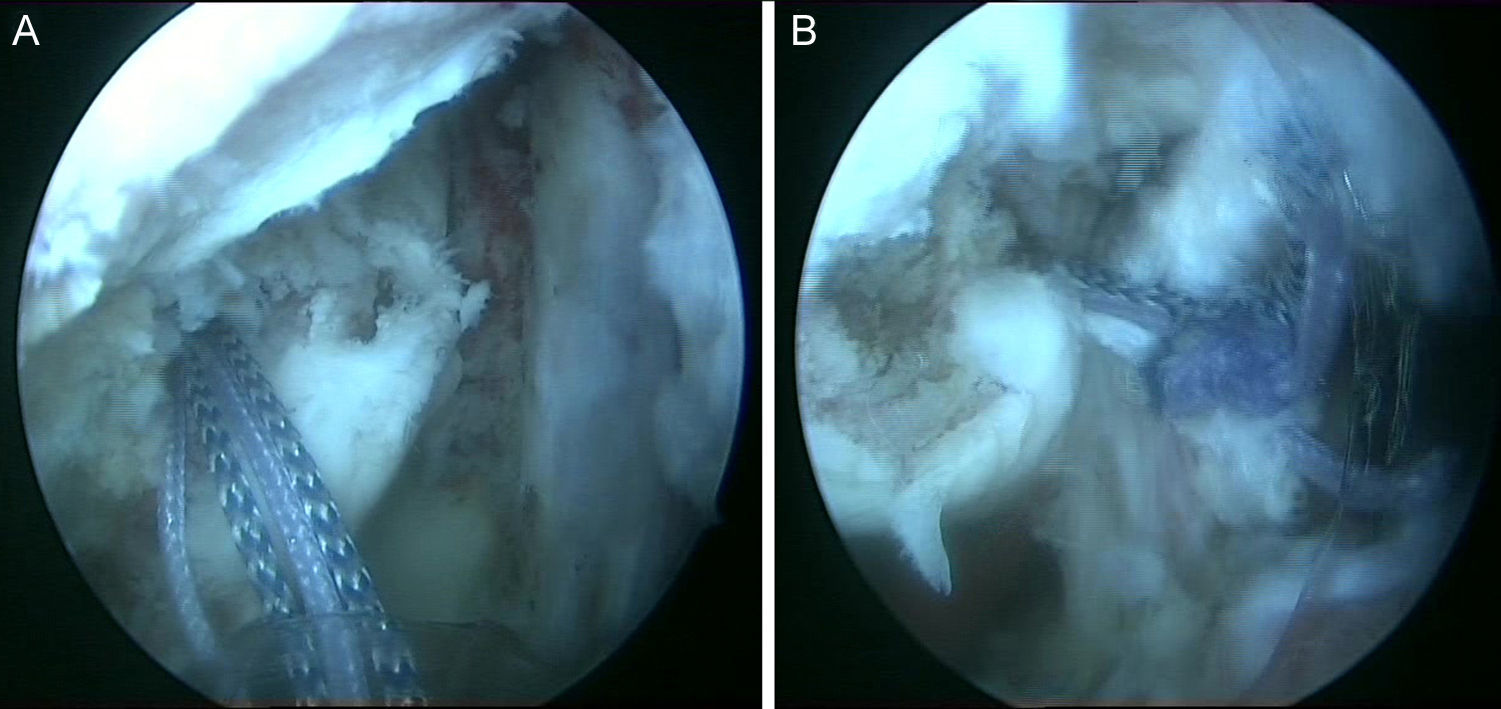

No es estrictamente necesario que reproduzcamos un enganche de la lesión de Hill-Sachs inversa para decidir realizar el remplissage inverso. Con la óptica en el portal anterosuperolateral liberamos el tendón del subescapular, su cara anterior y posterior. Preparamos el lecho óseo de la cabeza humeral, extirpando todo el tejido fibroso de la lesión de Hill-Sachs inversa, con el sinoviotomo, la fresa de hueso o periostotomos, hasta obtener hueso sangrante. Entonces desde el portal anterior, insertamos los implante en el defecto óseo (en el caso 1 un 5,5 Healix BR [DePuy Mitek, Raynham, MA] con 2 suturas UHMWPE [Orthocord; DePuy Mitek]) en el tercio superior y en la zona más medial del defecto (fig. 5), y en el caso 2 insertamos 2 Gryphon BR Healix BR (DePuy Mitek, Raynham, MA) con 2 suturas UHMWPE (Orthocord; DePuy Mitek), uno inferior y otro superior en la zona más medial del defecto óseo. Recuperaremos las suturas desde un portal anterosuperior accesorio y con una pinza para atravesar el tendón (Penetratror DePuy Mitek, Raynham, MA) a través del portal anterior, atravesamos el tendón del subescapular y recuperamos las suturas. Daremos puntos colchoneros, uno inferior y otro superior, para conseguir un buen contacto del tendón con el hueso, separando los puntos entre 1 y 2cm (fig. 6). Podemos ayudarnos con un empujanudos a través del portal anterosuperior accesorio para el manejo y recuperación de las suturas, acercándolas a la boca de la pinza penetrator, tratando de no mover en exceso la pinza una vez atravesado el tendón, para evitar lesionar el tendón y el cartílago. Manteniendo el brazo en 35-40° de rotación interna anudamos primero el punto inferior y luego el superior (figs. 7 y 8).

Caso 2, hombro izquierdo. A. Visión desde el portal ASL de la cara posterior del subescapular con los 2 implantes en la parte inferior y superior del defecto óseo. B. Imagen tras el anudado del punto más inferior. C.

Imagen de la cara anterior del subescapular tras el anudado del segundo punto.